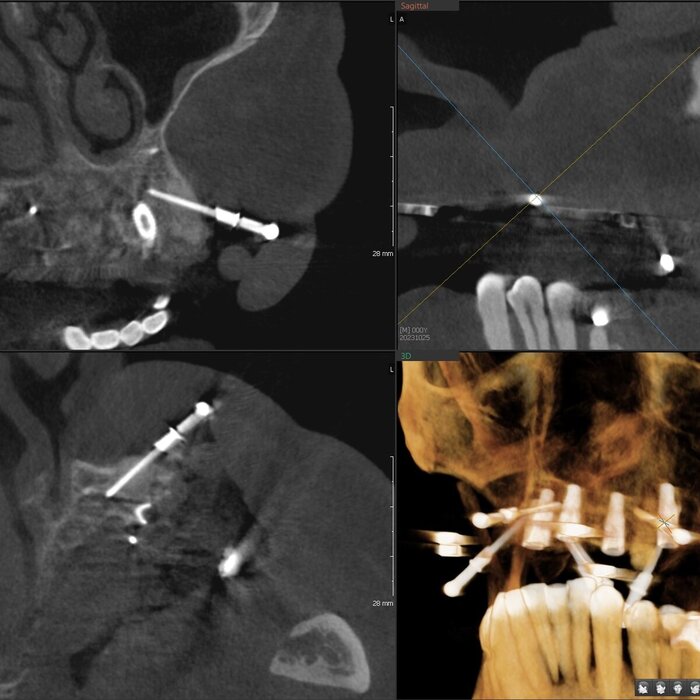

Посмотрим срезы.

Пародонтит.

Зубы цепляются за кость верхушками корней.

Пародонтит.

Куда ни глянь - одна картина.

Пародонтит.

Деструкция кости капитальная.

Пародонтит + периодонтит.

Хуже пародонтита может быть только присоединившийся к нему периодонтит (воспалительный процесс на верхушке корня/корней, в народе "киста") - вот уж где разрушение кости глобальным образом проявляется.

Периодонтит.

Кортикальные пластики утеряны, жаль.